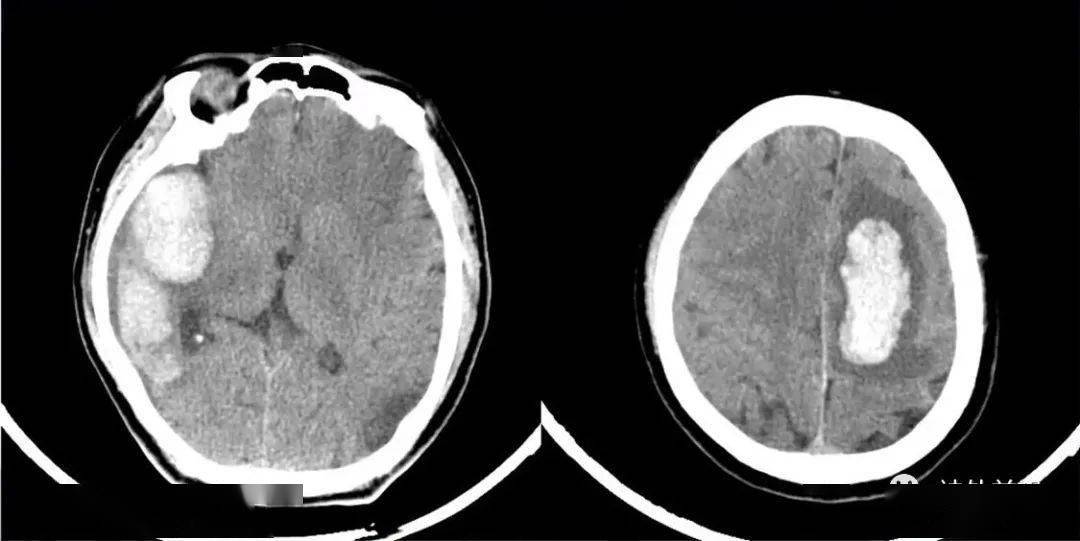

神经内镜下脑内血肿清除术术前术后影像对比. 邹仰光 摄

术前ct平扫,右侧基底节区脑内血肿,血肿量约16ml.

术前ct-1,血肿量约60ml.